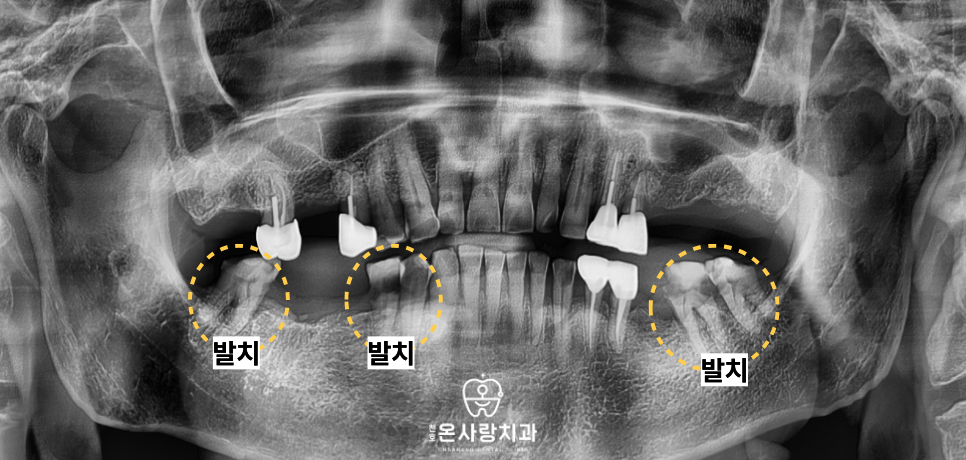

정밀 진단을 통해 하악 상태를 면밀히 분석한 결과

남아 있는 치아들의 손상 정도가 심해

정상적인 저작이 불가능하다는 판단을 내렸습니다.

치료 과정에서는 환자분이 느끼시는

하악의 통증 원인을 발치를 통해 먼저 제거하고

잇몸의 상태를 안정시키는 데 주력하였습니다.